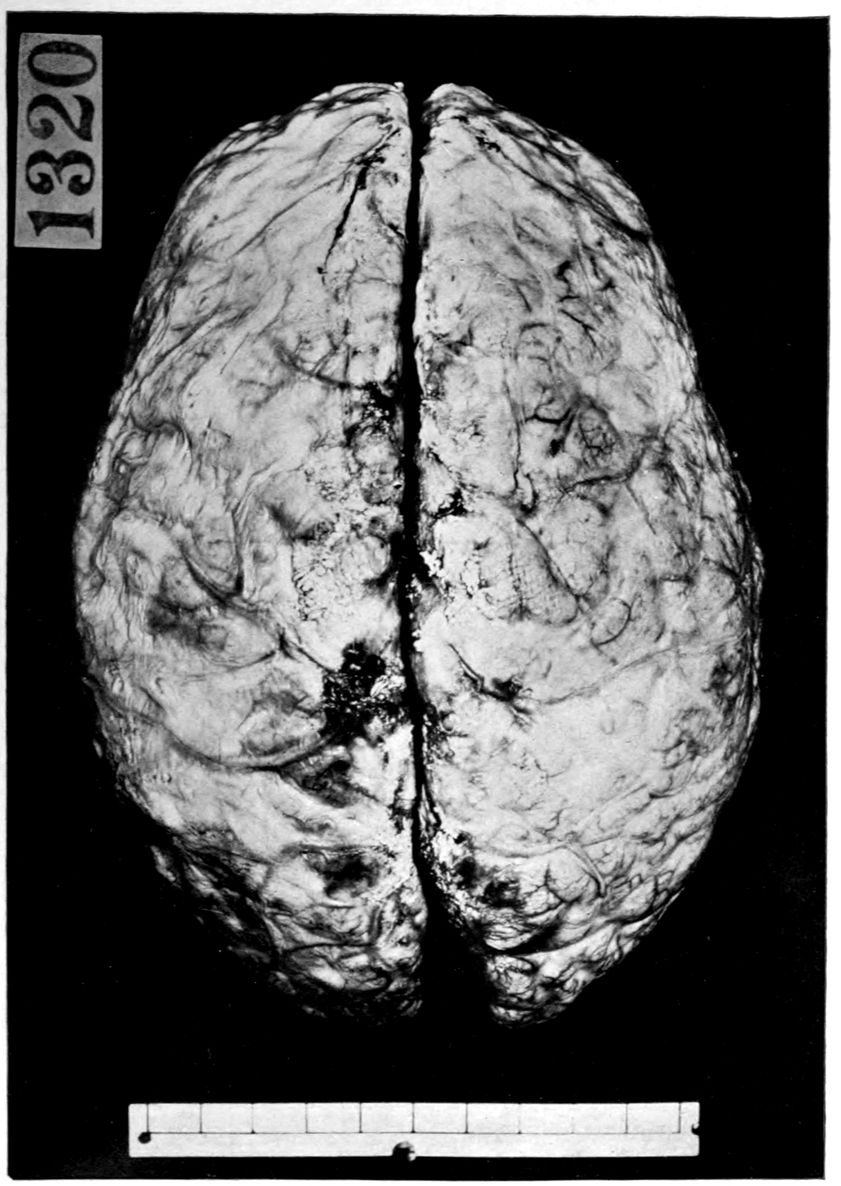

VASCULAR NEUROSYPHILIS (“syphilitic cerebral thrombosis”). Autopsy.

Case 4. James Pierce was an almshouse transfer to the Danvers Hospital in his fiftieth year. He died three years later. The accompanying brain pictures demonstrate so extensive a lesion of the left hemisphere that it is of great interest to determine if possible the genesis and course of his disease. It appears that syphilis had been acquired somewhere about the age of 38 or 40, so that the total duration of the process was between 13 and 15 years. In Pierce’s forty-third or forty-fourth year, he had a shock while walking in the streets of his native city, whereupon he was subsequently transferred to the Danvers Hospital, whose data have been summed up as follows (we are obliged to Dr. Charles T. Ryder for these data):

Neurological examination: Neuromuscular condition: Barely able to walk or stand without assistance; hemiplegia of right side; swings foot out and drags toe out and around in attempting to walk. Right hand held by side, flexed at right angle; fingers contracted and thumb thrown across palm. Can lift arm from side; practically no movements of forearms or fingers; atrophy of deltoid, arm, forearm, and hand. Muscular movements of left upper extremities fairly well performed; good strength.

Cranial nerves: Refuses to respond to any tests to determine hearing or vision, but evidently hears what is said to him, and in his movements gives no evidence of deafness. Right corner of mouth droops; tongue protrudes straight.

Reflexes: Pupils dilated; margins irregular; left pupil larger; they vary in size but it is impossible to determine whether the variation is due to light or accommodation reflex. Reflexes of right side extremely exaggerated throughout; there is little ankle clonus; Babinski is not obtained, patient holding his toes in flexed position in resisting attempts to elicit reflexes.

43Sensations: Reaction to pain stimuli on either side. Evidently some anesthesia on right side, but pressure is apparently very painful. There is considerable spasticity of limbs on right side on passive motion. Too demented to make accurate tests.

The above examination was made on May 6, 1904. On May 20th the record states:

There is almost complete sensory aphasia with word-deafness; some paraphasic circumlocution. Many of his words are very well enunciated but have no meaning. Is apparently unable to recognize objects or their uses.

Brother stated that he was always supposed not to be over bright. Physician’s certificate states that he is epileptic, averaging two attacks per week. On the 15th of May he had a general convulsion; was unconscious for half an hour, and dull and drowsy for two hours afterwards. On the 19th, he had a similar attack in the afternoon, the convulsion lasting a minute, and he was stuporous for an hour.

On November 8th he had a severe epileptic convulsion. His body was curled up to the right. The convulsive seizure lasted for two minutes and was followed by complete unconsciousness for an hour, when the patient roused and appeared as usual in a few minutes. From that time to December 15th he had five epileptic convulsions; he was much more feeble, and unable to help himself as much as formerly.

Nov. 7, 1905: Patient has had occasional convulsions since last note, but none during the last three months. He is confined to bed, has become very much demented, and shows very marked speech defect, so that he is almost unintelligible. He understands only the simplest directions. Legs are considerably contracted and knees are flexed. Arm and hand on the right are paralyzed and show some atrophic changes; partially flexed. Left elbow jerk is very lively. On May 23, 1906 he was reported as having Achilles on right side only, and Babinski on right side. He died January 5, 1907.

The autopsy findings were as follows:

Head: Calvarium of moderate thickness; diploë present; dura slightly adherent over bregmatic region. Longitudinal sinus contains cruor clot. Dura is somewhat thickened and slightly more opaque than normal. Pacchionian granulations, small but fairly numerous. Pia contains throughout a considerable excess of clear 44serous fluid. The convolutions in general are of good breadth and proportion. There is an atrophic area roughly circular in outline and about 2 cm. in diameter in the posterior part of the right third frontal convolution corresponding to Broca’s area on the opposite hemisphere. The space thus formed is filled with edema held by the pia. On the left side is a similar subpial collection which covers the site of the posterior portions of all of the third frontal convolutions, parts of the lower end of the precentral convolution, and the whole of the first temporal convolution, which have disappeared entirely. The basal vessels show slight changes.

Cerebellum and basal ganglia are grossly normal.

The spinal membranes are negative. The regions of the pyramidal tracts in the cord are firm, project slightly from surface of section, and are china white.

Summary: Here is a picture made up almost purely of Vascular Neurosyphilis, with Secondary Spinal (Pyramidal Tract) Changes. Doubtless the genesis of this picture is allied to that of Case 1 (Alice Morton) and to that of the terminal vascular complications in a tabetic, Case 2 (Francis Garfield).

The absence of meningeal and parenchymatous (i.e., outside the region of necrosis produced by the vascular disease) lesions is characteristic of an important group of neurosyphilitic diseases. It is clear that the case, although one of extensive lesions, is not one of diffuse lesions in the sense of Case 1 (Alice Morton).

The spinal fluid picture in life may nevertheless show (as other cases amply demonstrate) a certain amount of lymphocytosis and possibly plasmocytosis, together with a variety of other changes. Treatment might be expected to keep down these associated changes, although obviously the effects of the necrosis are final and definite. Franz in Washington has succeeded in “reeducating” some of these hemiplegics, employing lower mechanisms of the nervous system.

Vascular neurosyphilis—effects of syphilitic thrombosis of Sylvian artery 10 years before death. (Case 4.)

Case 4. (See previous figure for brain lesion.) Three levels of the spinal cord showing unilateral pyramidal tract sclerosis, 10 years after cerebral thrombosis.